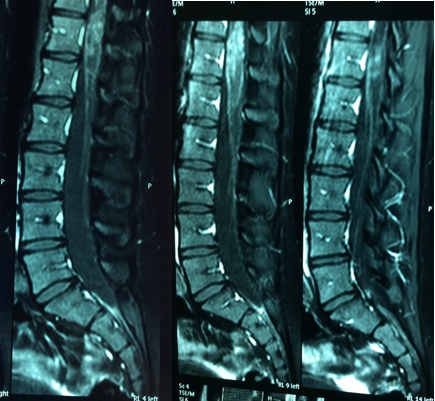

A esquistossomose é uma das doenças parasitárias mais comuns no mundo. É um importante problema de saúde pública. A neuroesquistossomose refere-se ao envolvimento do sistema nervoso central, que quando sintomática é grave, e o prognóstico depende do tratamento precoce. Paciente feminino, 20 anos, iniciou um quadro de dor intensa em região lombar, evoluindo após uma semana com paresia em membro inferior esquerdo e retenção vesical, seguida de paresia em membro inferior direito. Ressonância de coluna toraco-lombar evidenciou alteração de sinal envolvendo a medula espinhal, e espessamento no cone medular e em raízes da cauda eqüina. A sorologia para Esquistossomose foi positiva. Excluídos diagnósticos diferenciais, foi definido o diagnóstico presuntivo de Mielorradiculopatia esquistossomótica. A paciente respondeu satisfatoriamente ao tratamento com pulso de Metilprednisolona por cinco dias, Praziquantel em dose única e Prednisona em dose imunossupressora, com duração prevista para 6 meses. O reconhecimento de neuroesquistossomose é importante para que a terapêutica seja iniciada precocemente para evitar a deficiências graves. O caso relatado reforça a importância do conhecimento da mielorradiculopatia esquistossomótica, uma doença ainda subdiagnosticada no nosso meio.